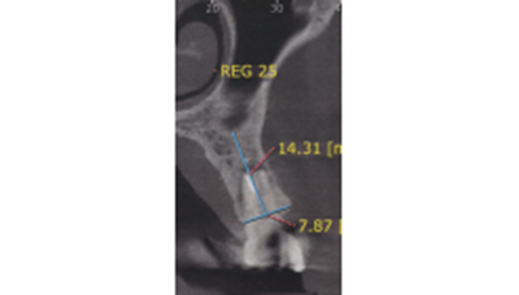

Paciente do sexo feminino, com viagem marcada para o exterior, apresentou-se em minha clínica com o diagnóstico de lesão e grande mobilidade do elemento 25. Após a solicitação dos exames preliminares e da anamnese, foi realizada a conduta medicamentosa e a cirurgia foi marcada para instalação imediata do implante (Figuras 3 e 4).

Foi eleito um implante Veloce Cone Morse de 3.75 X 11.5 mm e após a exodontia, o implante foi instalado utilizando o protocolo de fresagem recomendado pelo fabricante, fazendo uso das fresas escalonadas do sistema, alcançando um torque de inserção de 70 Ncm, o que me incentivou a promover o carregamento imediato deste implante (Figuras 5, 6, 7, 8, 9 e 10).